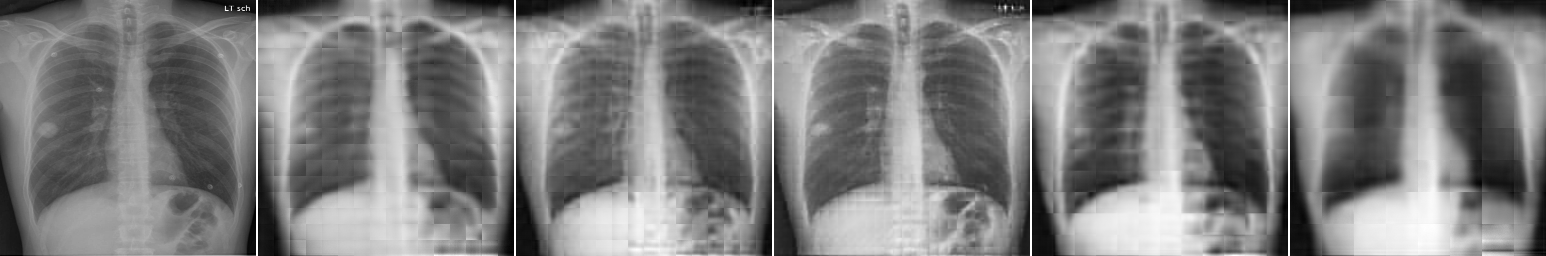

Image Patch Regeneration: Here, we vary the block size for image encoding and decoding to see how it will affect the image regeneration task. As shown in Fig. 5 and Table 4(b), block size renders the best image regeneration quality compared to other variants. Block size demonstrates higher classification accuracy with a moderate requirement of the computing resources (larger # patches per image will require larger GPU memories). As shown in Fig. 5, our proposed multi-scale image encoder and decoder can provide better regeneration results than a single-scale model. It generally suffers less from the blocking artifacts and is able to preserve more details, especially for pathological regions, as shown on the top two examples in Fig. 5.

3.3 Multi-scale Image Encoding and Decoding

The positional encoding used by existing works for image patch locations may not be sufficient to preserve the spatial information of images. This is because nearby image patches are often closely related, but direct patch predictions solely based on the features of each cell are not effective enough, which often lead to blocking artifacts (as shown in the result section later). It is one of the natural disadvantages of transformer-based methods for image processing compared to CNN-based ones. Here, we attempt to suppress this shortcoming within the general framework of transformer architectures. In Fig. 4, we illustrate a multi-scale image encoding and decoding process.